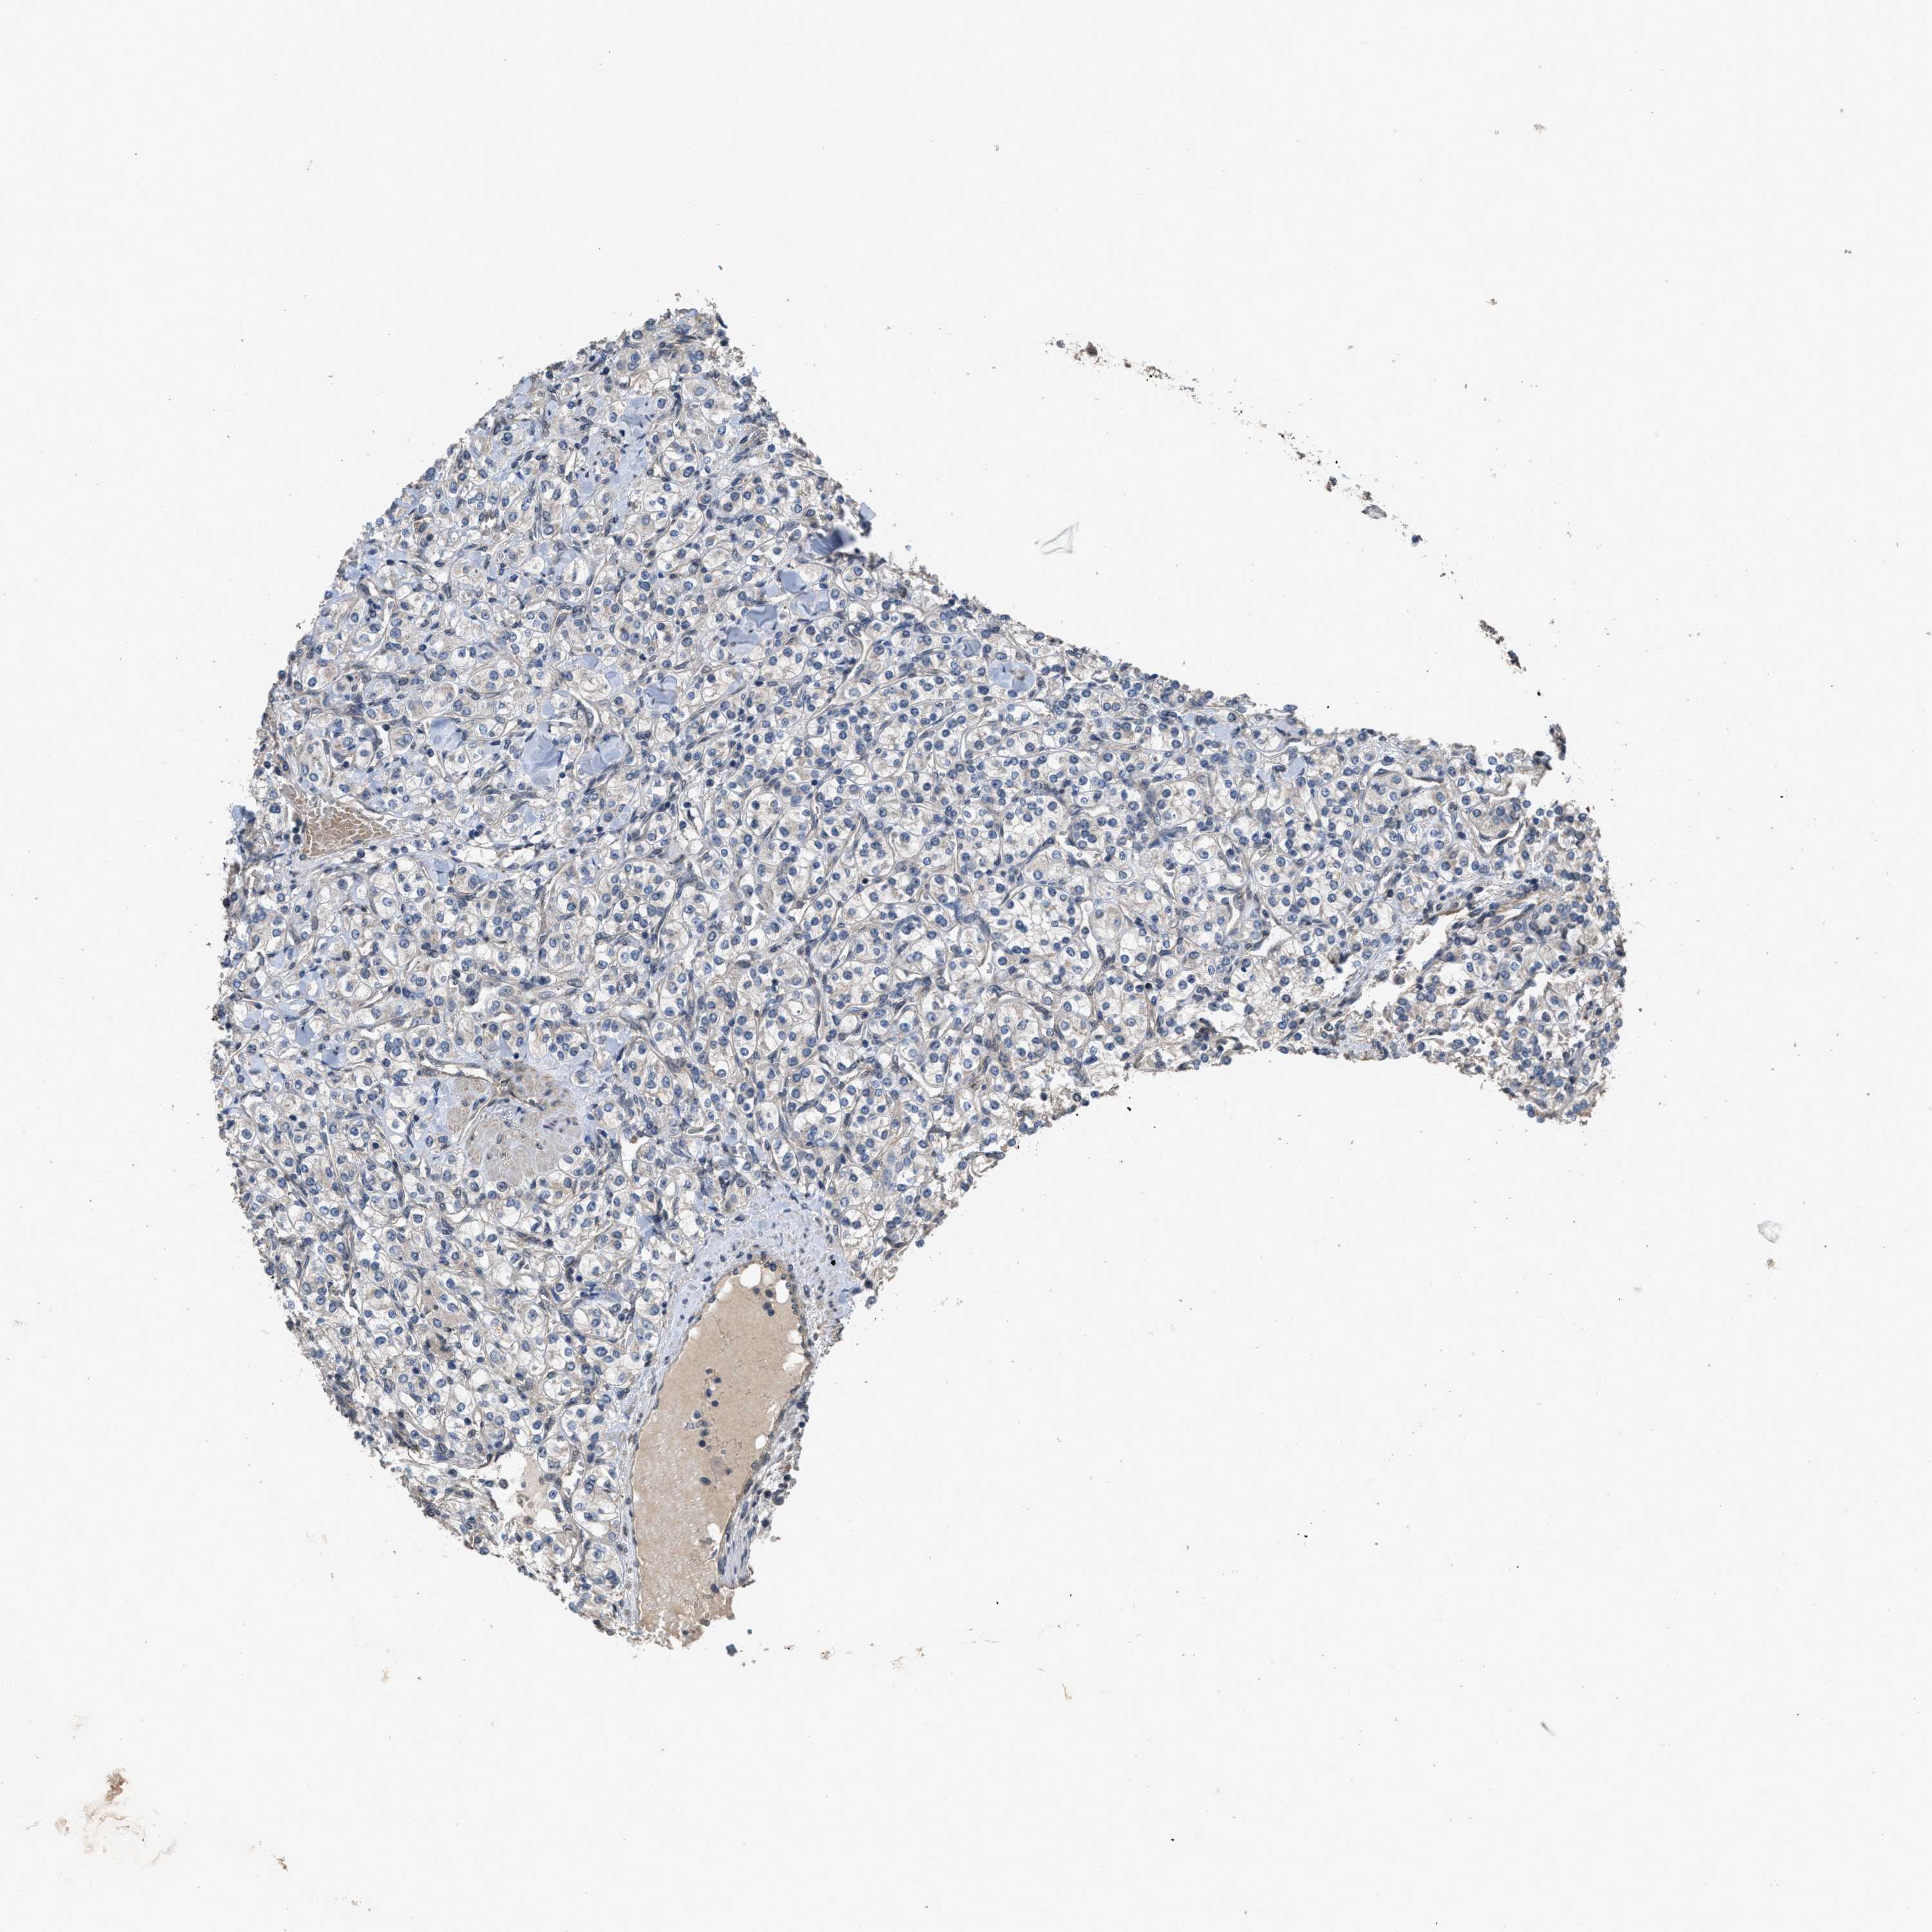

KIDNEY RENAL CLEAR CELL CARCINOMA (TCGA) - Interactive survival scatter ploti

The Survival Scatter plot shows the clinical status (i.e. dead or alive) for all individuals in the patient cohort, based on the same data that underlies the corresponding Kaplan-Meier plots. Patients that are alive at last time for follow-up are shown in blue and patients who have died during the study are shown in red.

The x-axis shows the expression levels (FPKM) of the investigated gene in the tumor tissue at the time of diagnosis. The y-axis shows the follow-up time after diagnosis (years). Both axes are complimented with kernel density curves demonstrating the data density over the axes. The top density plot shows the expression levels (FPKM) distribution among dead (red) and alive patients (blue). The right density plot shows the data density of the survived years of dead patients with high and low expression levels respectively, stratified using the cutoff indicated by the vertical dashed line through the Survival Scatter plot. This cutoff is automatically defined based on the FPKM cutoff that minimizes the p-score. The cutoff can be changed by dragging the vertical line or by entering a cutoff value in the square labeled "Current cut-off".

Under the Survival Scatter plot the p-score landscape (black curve; left axis) is shown together with dead median separation (red curve; right axis). Dead median separation is the difference in median mRNA expression between patients who have died with high and low expression, respectively. It is calculated as follows: median FPKM expression of dead patients with high expression - median FPKM expression of dead patients with low expression. This is intended to aid the user in visually exploring custom cutoffs and the associated p-scores and dead median separation.

Individual patient data is displayed and can be filtered by clicking on one or more of the category buttons on the top of the page. Categories describing expression level and patient information include: high, low, alive, dead, female, male and tumor stages. The scale of the x-axis can be toggled between linear and log-scale by clicking on the "x log" button. Mouse-over function shows TCGA ID, patient information and mRNA expression (FPKM) for each patient.

& Survival analysisi

Kaplan-Meier plots summarize results from analysis of correlation between mRNA expression level and patient survival. Patients were divided based on level of expression into one of the two groups "low" (under cut off) or "high" (over cut off). X-axis shows time for survival (years) and y-axis shows the probability of survival, where 1.0 corresponds to 100 percent.

UTRN is validated prognostic, high expression is favorable in Kidney Renal Clear Cell Carcinoma (TCGA)

: 38.77

Average pTPM 40.8

Number of samples 521